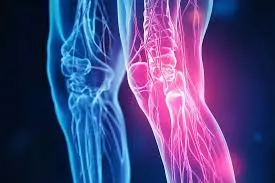

મોબિલિટી એક્સરસાઇઝ (Mobility exercises) આધુનિક ફિટનેસ અને રિહેબિલિટેશન (પુનર્વસન) દિનચર્યાઓનો એક આવશ્યક ભાગ બની ગઈ છે. ભલે તમે રમતવીર હોવ, ફિટનેસના શોખીન હોવ અથવા બેઠાડુ જીવનશૈલીને કારણે જડતાનો સામનો કરી રહ્યાં હોવ, તમારી ગતિશીલતા (mobility) સુધારવાથી તમારા જીવનની એકંદર ગુણવત્તામાં નોંધપાત્ર વધારો થઈ શકે છે. સાચા અર્થમાં ફક્ત સ્ટ્રેચિંગ કરવા કરતાં અલગ, મોબિલિટી એક્સરસાઇઝ સાંધાની…